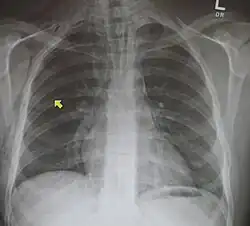

Pneumomediastino

Pneumomediastino (do grego pneuma ar) ou enfisema mediastinal é uma presença anormal de ar entre os pulmões (no mediastino). Descrito pela primeira vez em 1819 por René Laennec.[1] A condição pode resultar de trauma físico ou outra lesão que cause que ruptura das vias respiratórias (como tráquea, laringe ou pulmões) ou da via digestiva (como esôfago e estômago) para a cavidade torácica.